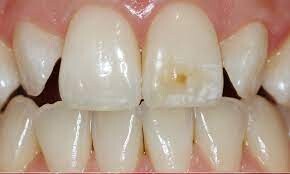

Tooth Decay

Decay starts when some oral bacteria multiply and generate higher acid levels. Once it starts progressing to cause an infection, you experience tooth pain. Without treatment, the bacteria may also cause a dental abscess in the pulp. It typically makes the tooth more painful than ever before.